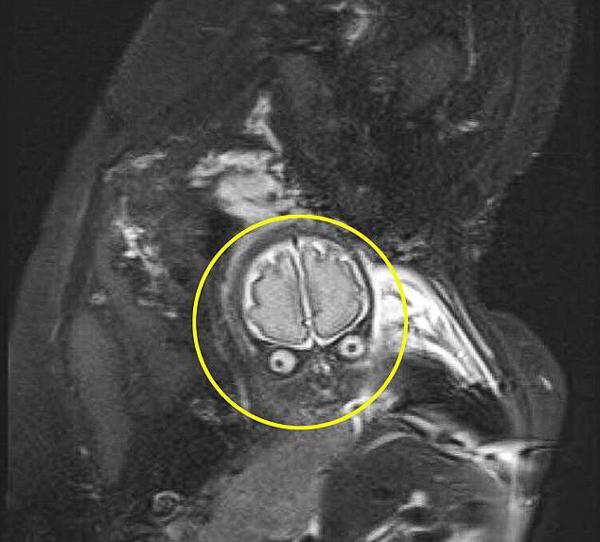

Khi mang bầu, Laura Thomas (26 tuổi) phải siêu âm liên tục do thuộc nhóm có nguy cơ tiền sản giật cao. Trong một lần siêu âm, các bác sĩ phát hiện lượng chất lỏng thừa bất thường tại khu vực não bộ của bé Lucas (con trai Laura) nên quyết định chụp cộng hưởng từ (MRI) để quan sát thêm.

"Ngày 13/2, bác sĩ phát hiện bất thường. Ngày 28/2 thì tôi được chụp MRI. Suốt 2 tuần chờ đợi, tôi đã vô cùng lo lắng. Các chuyên gia tư vấn cũng cảnh báo tôi rằng hình ảnh khi chụp cộng hưởng từ sẽ khác biệt rất nhiều với siêu âm 2D thông thường nhưng tôi không tưởng tượng được nó lại như vậy", Laura chia sẻ.

Trong bức ảnh, Lucas nhìn có vẻ như khá "giận dữ" với đôi mắt trợn tròn và bộ não hiện ra rõ ràng.

"Ấn tượng đầu tiên của tôi là có vẻ như con không được thoải mái lắm. Chồng tôi nhìn vào và lập tức thốt lên là nhìn con giống hệt một nhân vật ngoài hành tinh trong bộ phim Mars Attacks",Laura kể lại.

Mar Attacks (Cuộc tấn công từ sao Hỏa) là một bộ phim hài, khoa học viễn tưởng nổi tiếng từ năm 1996 của Mỹ Và thực sự nhìn Lucas trong bức ảnh chụp MRI không khác gì nhân vật người ngoài hành tinh trong phim.

"Tôi khá hốt hoảng nên lập tức hỏi bác sĩ xem có đúng đây là con không. Thật nhẹ nhõm khi bác sĩ khẳng định thằng bé ổn, không có gì bất thường và đương nhiên không phải... người ngoài hành tinh", Laura cười nói.